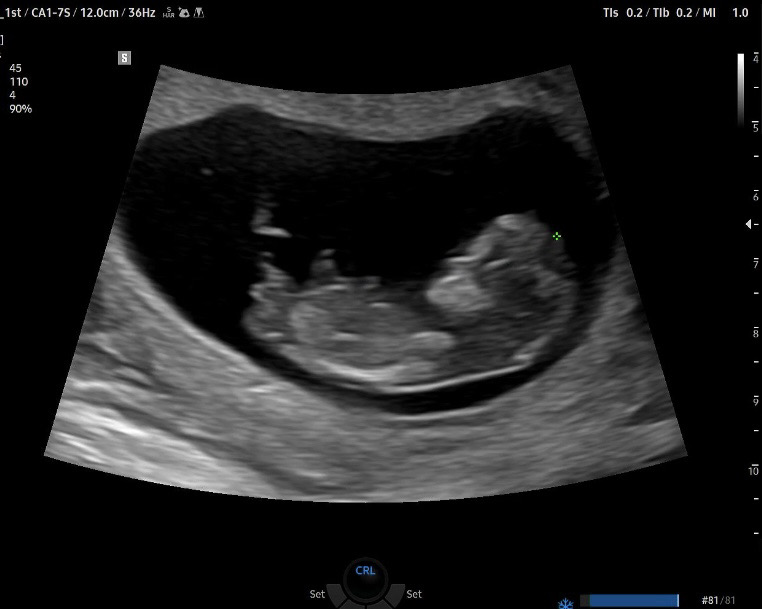

각도법 봐주세용!

11주 입니다ㅎㅎ 부탁드려요☺️👼🏻